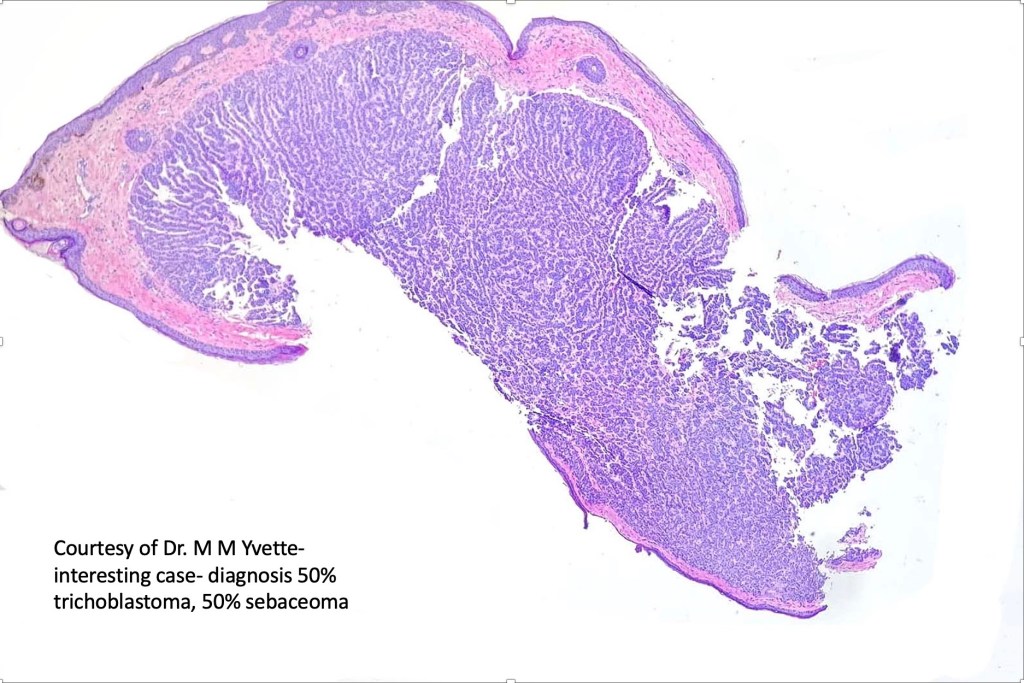

Sebaceoma

Clinical features

•Usually single

•Flesh colored to yellow papule or nodule 1-3 cm diameter on the face or scalp

•29-87 years, most 6-9th decade

•Associated with Muir-Torre syndrome

•May develop in nevus sebaceus & in the ocular adnexa

Histological features

•Variable continuity with epidermis

•Multinodular with surrounding collagenous stroma

•Random distribution of basaloid cells & sebocytes (<50% sebocytes)

•Duct formation, often with holocrine secretion generally present

•Mitoses sparse to conspicuous

•Absent peripheral palisading & retraction artifact